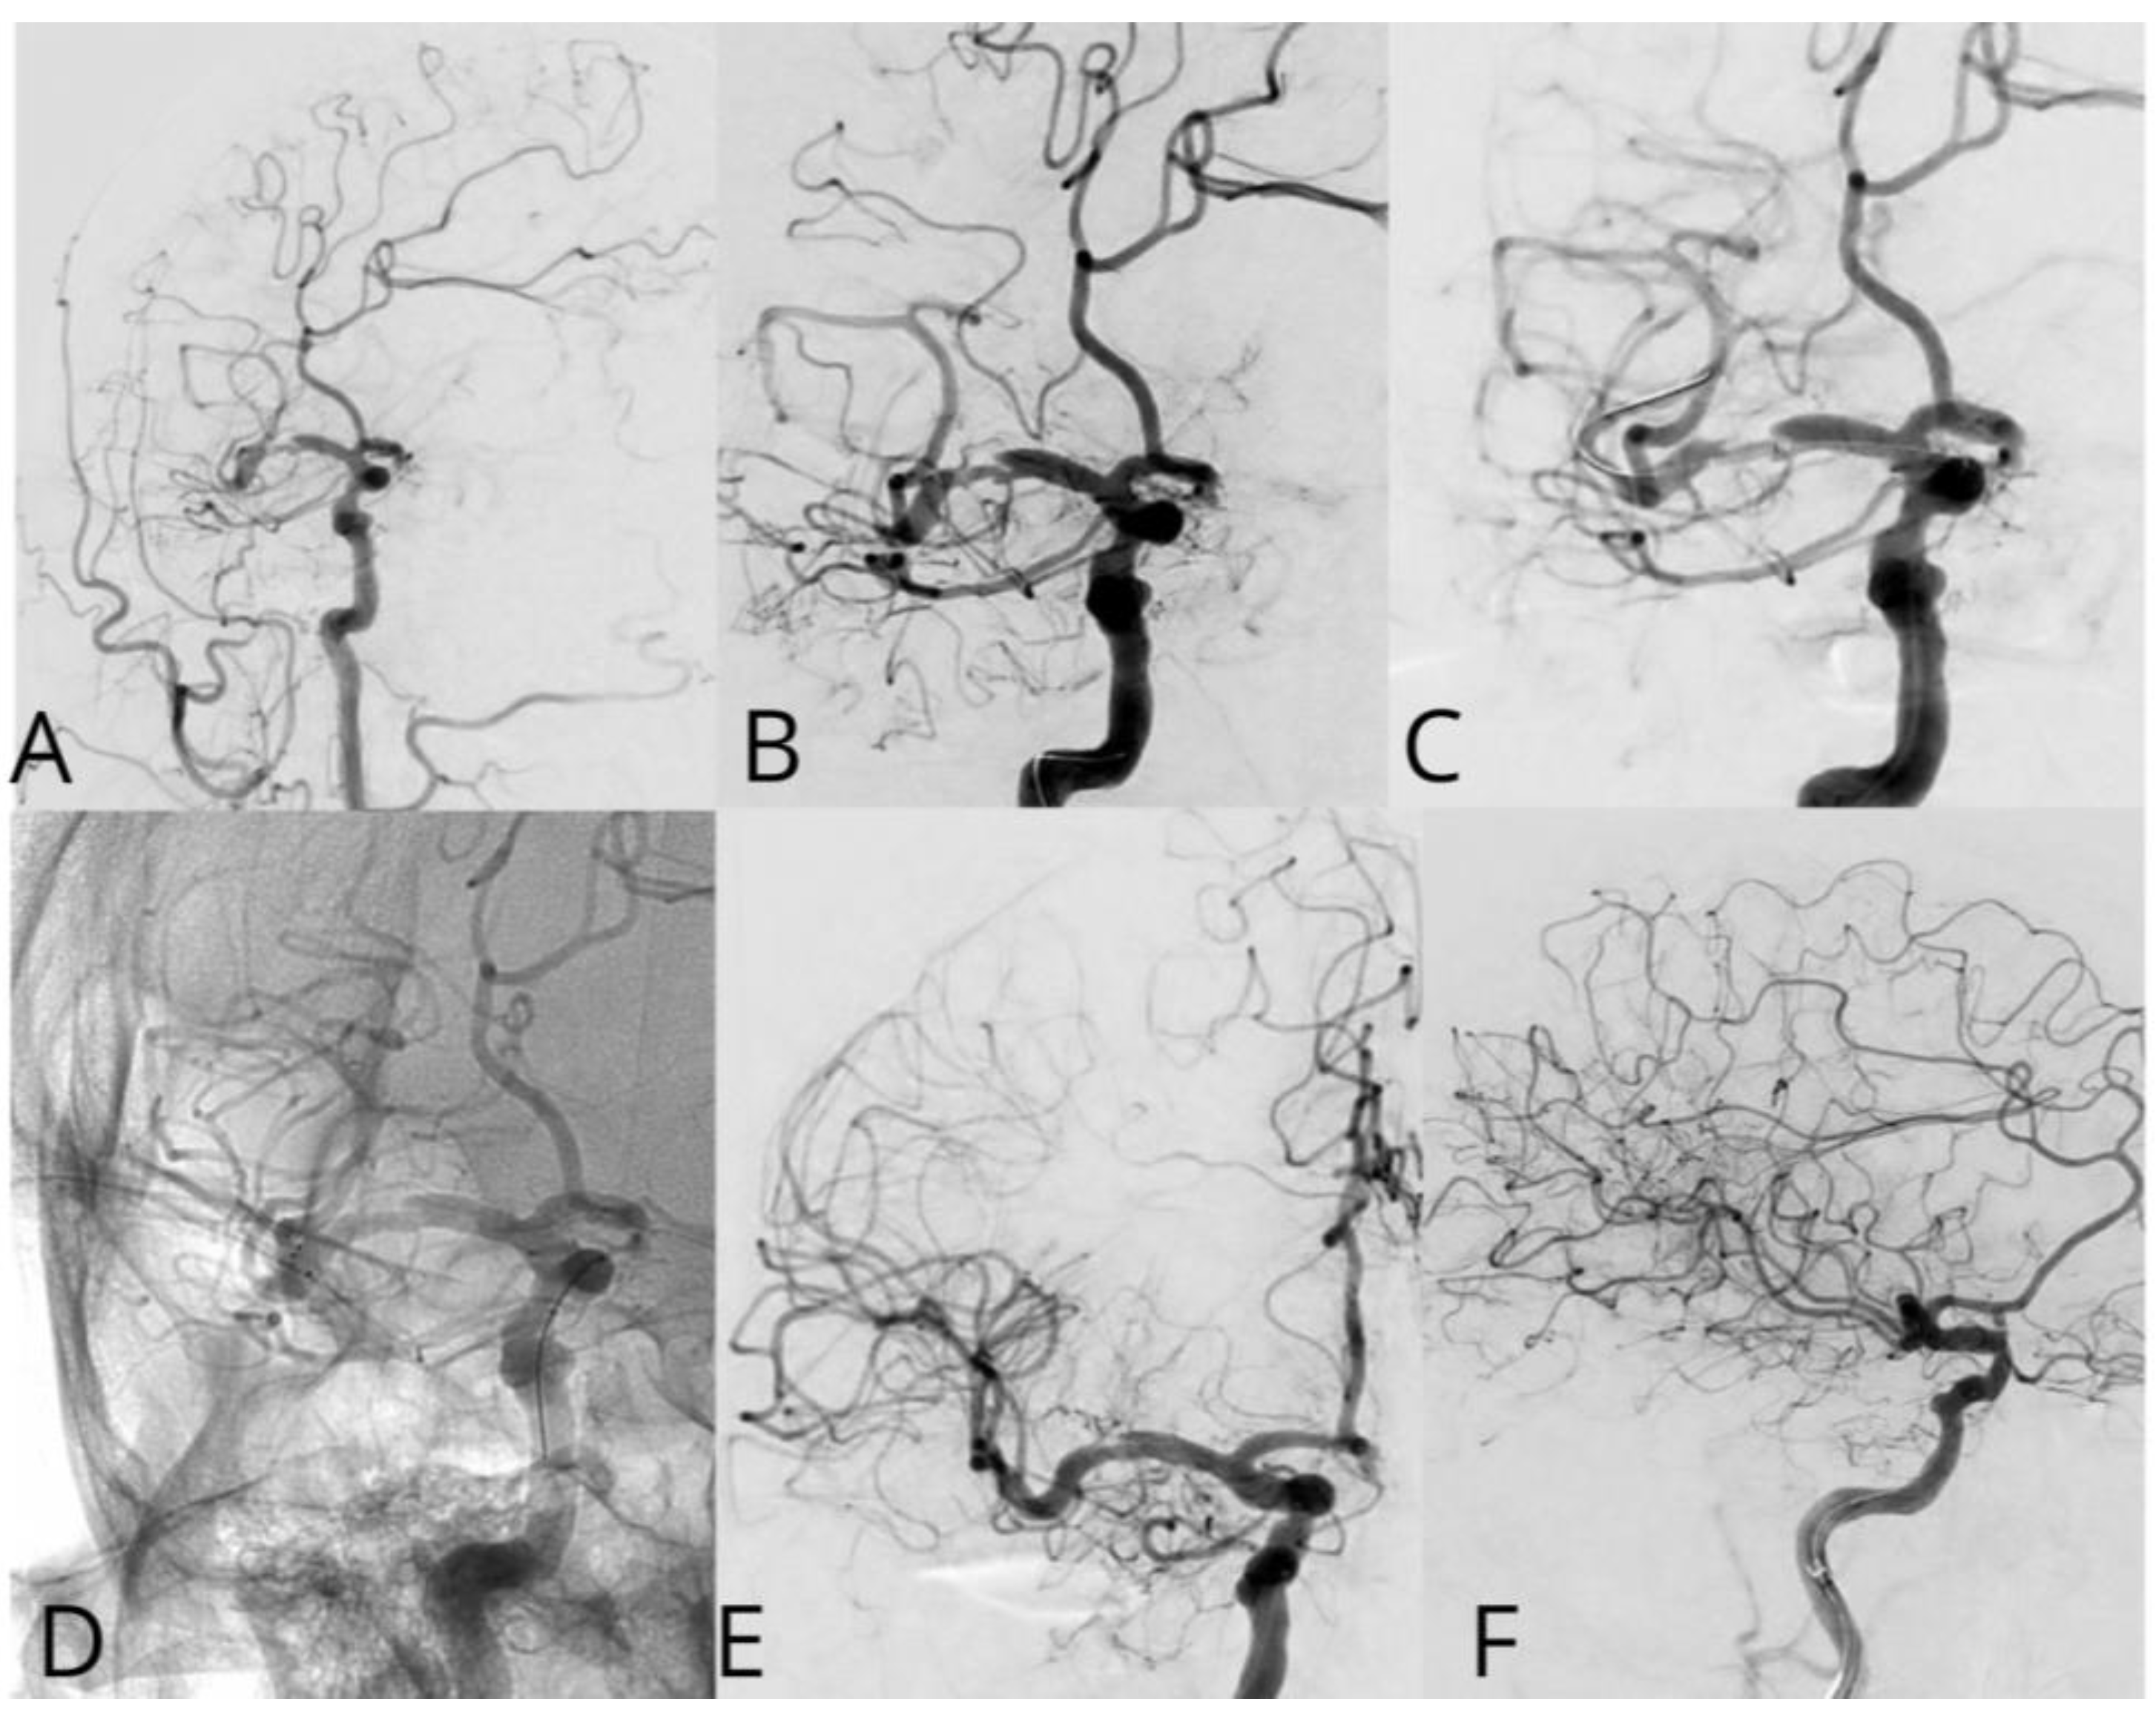

Case #2. A 48-year-old male patient presented with persistent pulsatile sensation in the parietal region, tinnitus, dizziness, blood pressure instability, right-sided weakness, general weakness, decreased work capacity, sleep disturbances, and memory loss. The patient had a history of hypertension for over 10 years and had experienced an ischemic stroke in the left middle cerebral artery territory two months prior, which was managed conservatively. Magnetic resonance imaging revealed signs of chronic ischemia in the right parietal and temporal lobes with cystic-gliotic changes, as well as single foci of hemosiderin deposition in the white matter of the cerebral hemispheres and basal ganglia, likely indicating microhemorrhage in the chronic stage. The patient underwent a comprehensive evaluation by a multidisciplinary team, including a cardiologist, neurologist, and pharmacologist, and was subsequently placed on ticagrelor. The procedure was performed under local anesthesia. An 8 French introducer was placed in the right femoral artery, and 8 French Hyperion catheters were navigated and positioned in the left internal carotid artery, covering the area of dissection and stenosis. DSA revealed a left M1 segment stenosis (Figure 2A,B). An Asahi Chikai Black 0.014 microwire was then advanced and placed in the M2 segment of the left middle cerebral artery. A dual-lumen coaxial microcatheter, the NeuroSpeed 2.0 x 8.0 mm, was navigated to the stenotic region and inflated twice using an inflator, resulting in a residual stenosis of up to 40%. Next, during the attempt to deploy an Acclino Heal 5.0x20mm stent through a balloon catheter starting from the M1 bifurcation of the left middle cerebral artery, the proximal portion of the stent became fixed within the balloon catheter due to the radiopaque markers. As a result, the balloon microcatheter and the damaged stent were removed (Figure 2C). Subsequently, a GAMA 17 catheter was navigated through the Asahi Chikai Black 0.014 microwire, and an intravascular Acclino Heal 5.0x20mm stent was reinserted and deployed to eliminate the stenosis (Figure 2D). The final angiographic evaluation demonstrated a patent left middle cerebral artery without any residual narrowing (Figure 2E,F).

Figure 2. A diagnostic cerebral angiogram demonstrates an 80% stenosis of the right MCA (A, B) in a patient who presented with recurrent TIAs as evidenced by left-sided weakness/numbness. A diagnostic cerebral angiogram performed after stent placement and angioplasty demonstrates (C, D) resolution of stenosis. The operation was performed with an Acclino stent (E, F).